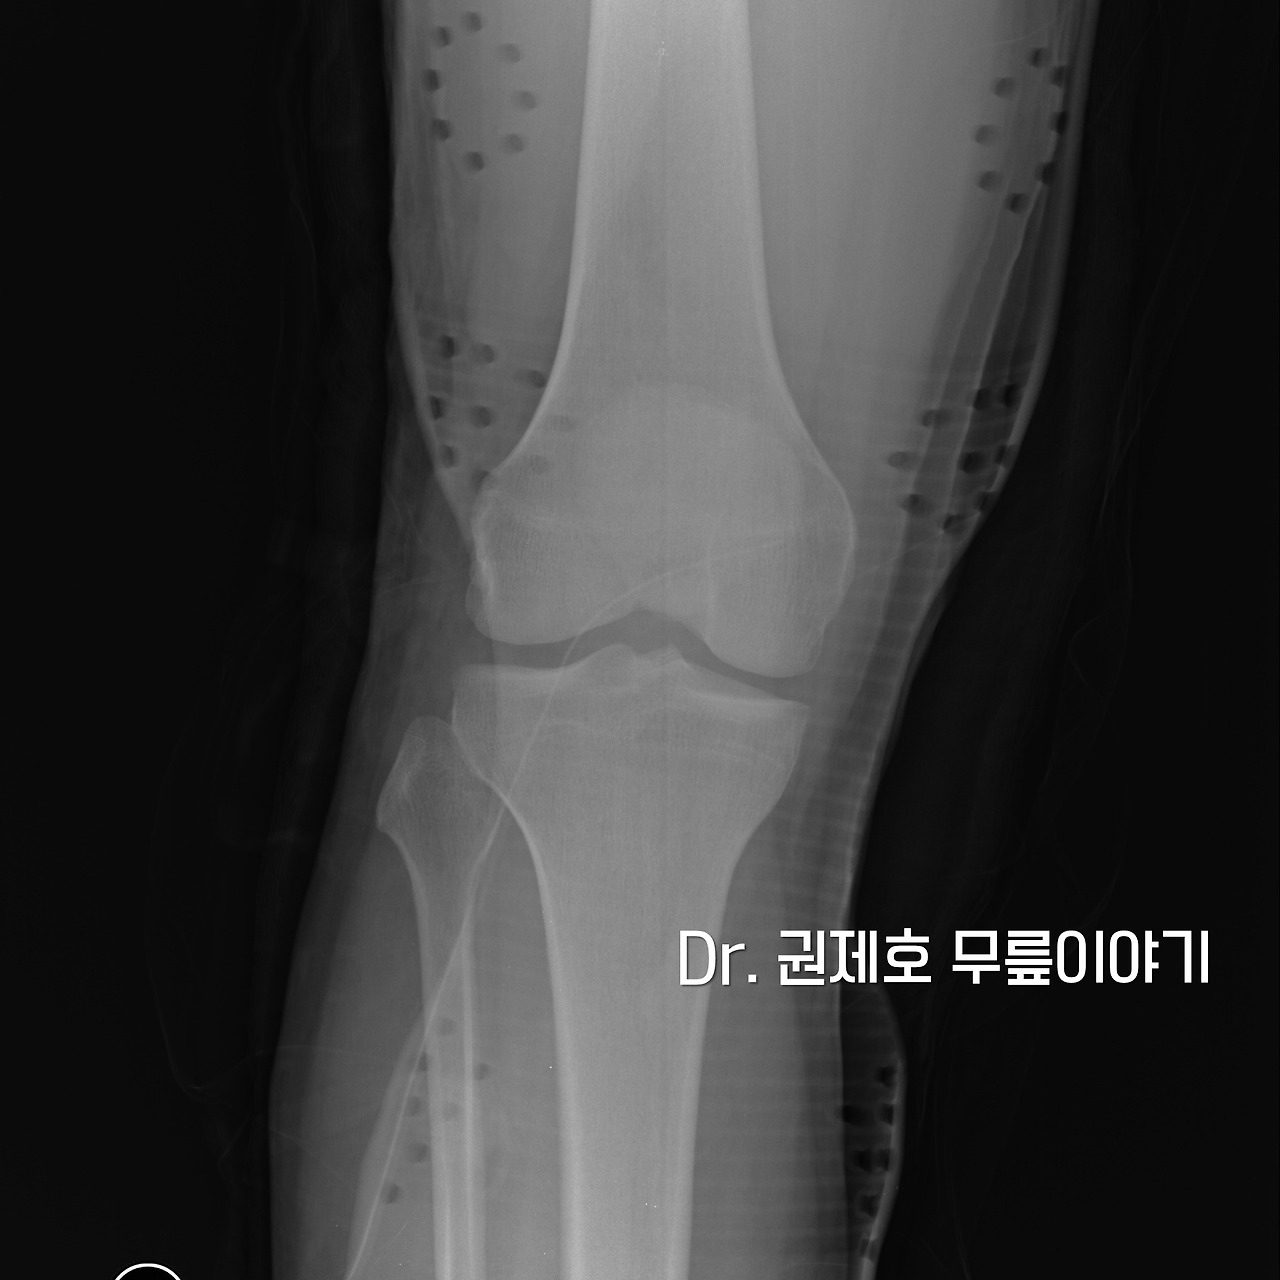

사진을 찍어보니 젊은 사람이어서 그런지 정상이다.